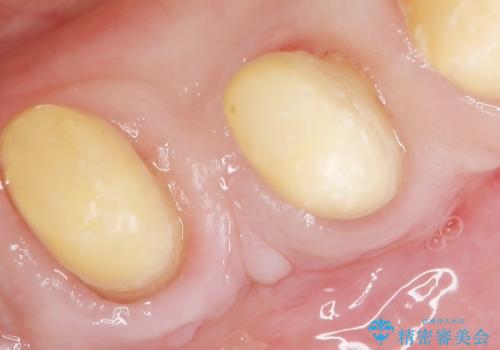

再生療法から1年後リエントリー手術により骨の再生を確認し、骨外科処置(骨を平らにして歯周ポケットの根本的な改善を図る処置)を行ったのち、連結補綴を行いました。

再生療法と骨外科処置により、歯周ポケットは全周2mm以下に改善されました。

クラウンの種類:メタルボンドクラウン エコノミー